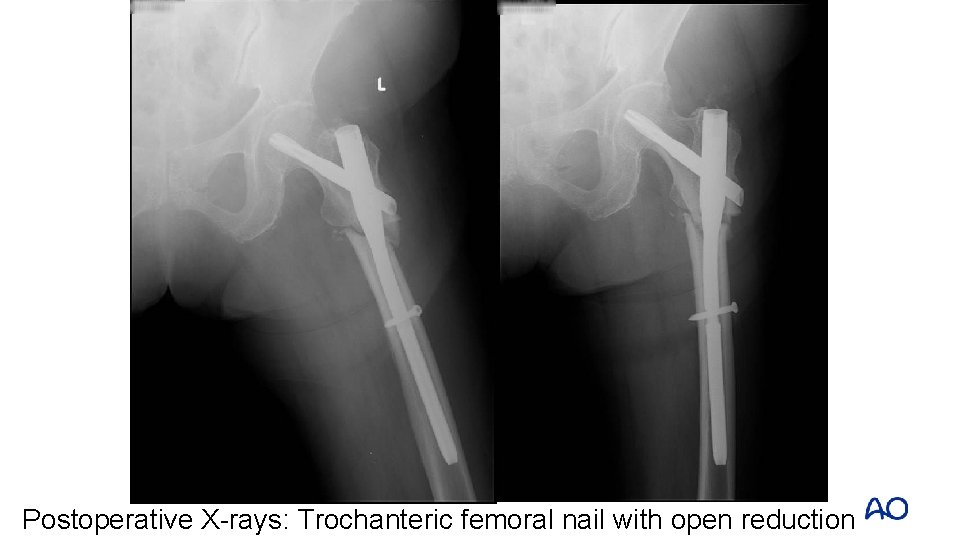

Postoperative X-rays: Trochanteric femoral nail with open reduction